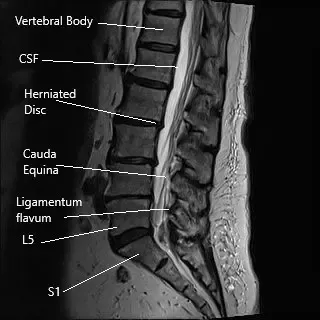

Microdiscectomy is a minimally invasive spine surgery commonly done for the surgical management of sciatica. Sciatica usually occurs as a result of the prolapse of an intervertebral disc. The intervertebral disc may prolapse as a result of age-related wear and tear or due to trauma as a result of fall or repetitive action.

Sciatica is usually managed with nonsurgical treatment and surgical treatment is only indicated in patients who have had no relief with the non-surgical measures. Microdiscectomy surgery involves a small incision in the lower back. The spine surgeon separates or cuts the muscles and tissues to reach the diseased disc. The herniated disc is then removed and pressure over the spinal nerve is relieved.